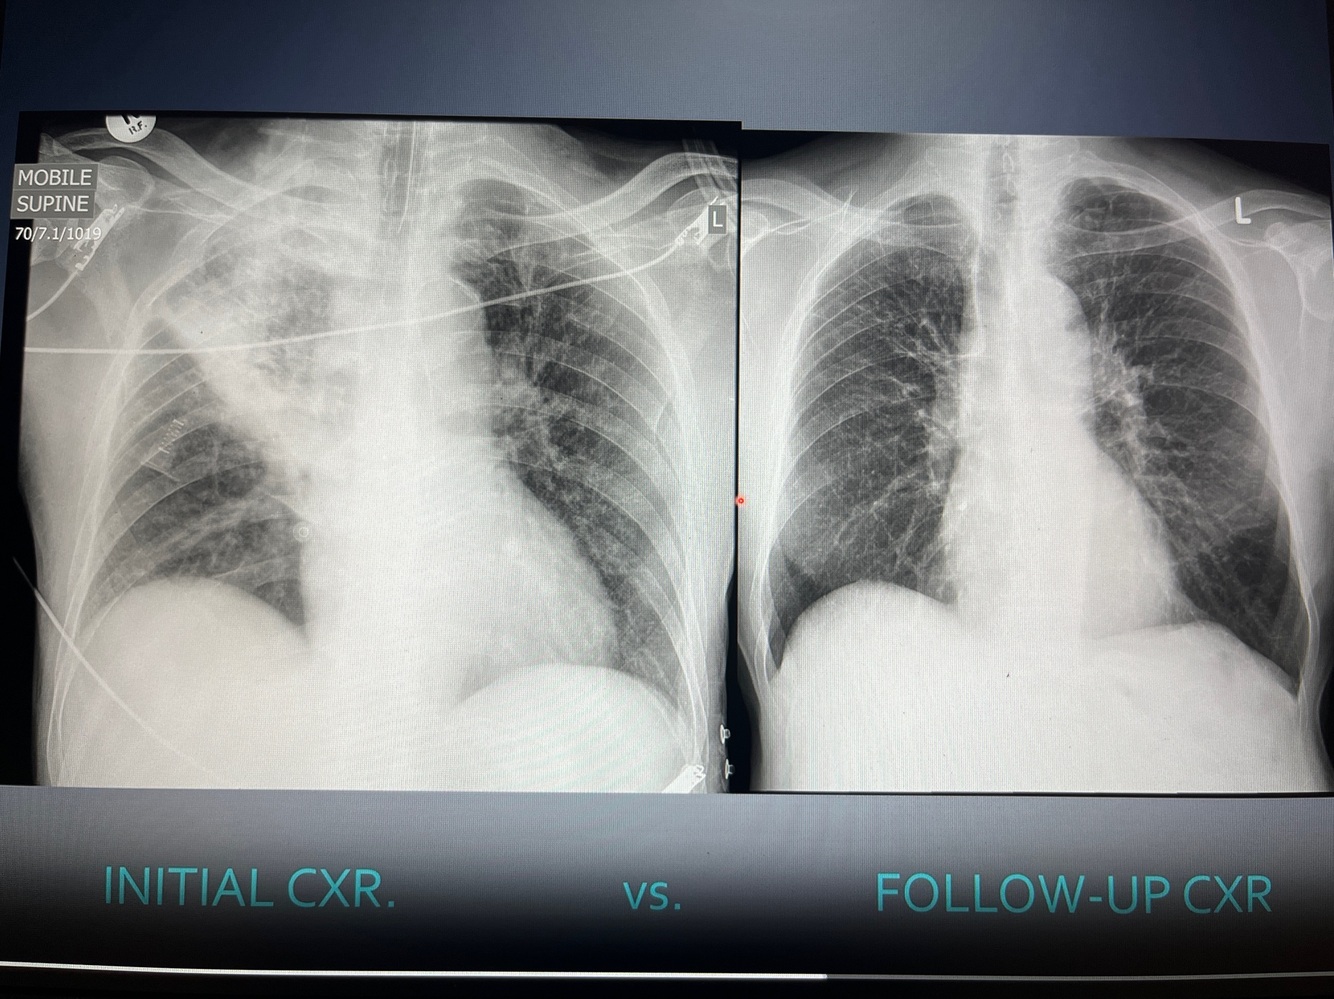

Opacification over lower lobes

Pneumonia with some form of collapse